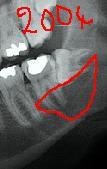

j'ai le scan mais pas ici la corticale linguale est reduite à sa plus simple expression et le kyste remonte sur le trajet du nerf et s'etend aussi en vestibulaire

à priori 31/03/2006 pas si vieux que ça je croyais que c'etait 2004, donc évolution rapide

ça peut être également un kyste dentigère laissé en place car il me semble que le kyste est déjà présent sur la première pano et elle est en rapport partiel avec le collet de 38 enclavée mais ça n'est pas caractéristique.